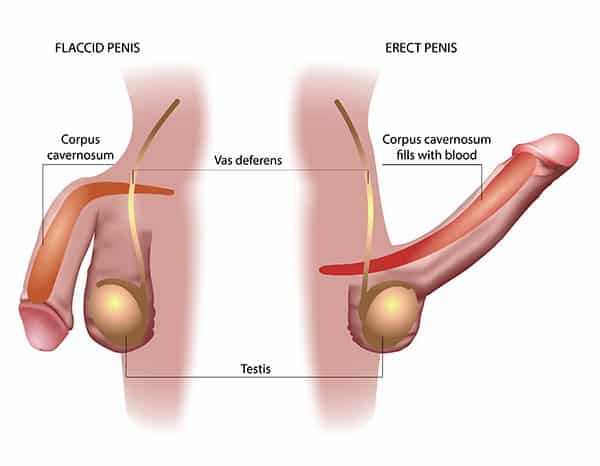

The three systems of an erection

For an erection to happen — and stay — three systems have to work together:

Blood flow in – arteries must open wide enough to flood the penis with blood.

Blood stay – tiny valves in the veins must lock shut, trapping the blood inside.

Signals from the brain – nerves must fire clearly, telling the body “now is the time.”

When these three align, you get a natural, reliable erection.

When even one fails… firmness collapses.

How they break down

Damaged blood vessels: age, stress, high cholesterol or diabetes narrow the arteries, starving the penis of blood.

Weak valves: veins can’t hold the pressure, so the blood escapes within minutes.

Silent nerves: after surgery, illness, or simply time, the nerves go numb, cutting off the vital signal from the brain.

Each gentle pulse triggers something remarkable:

New blood vessels form → increasing circulation where it matters most.

Valves strengthen → locking the blood in place, so erections stay firm.

Nerves reactivate → reconnecting the brain to the body, restoring the “signal” for desire.